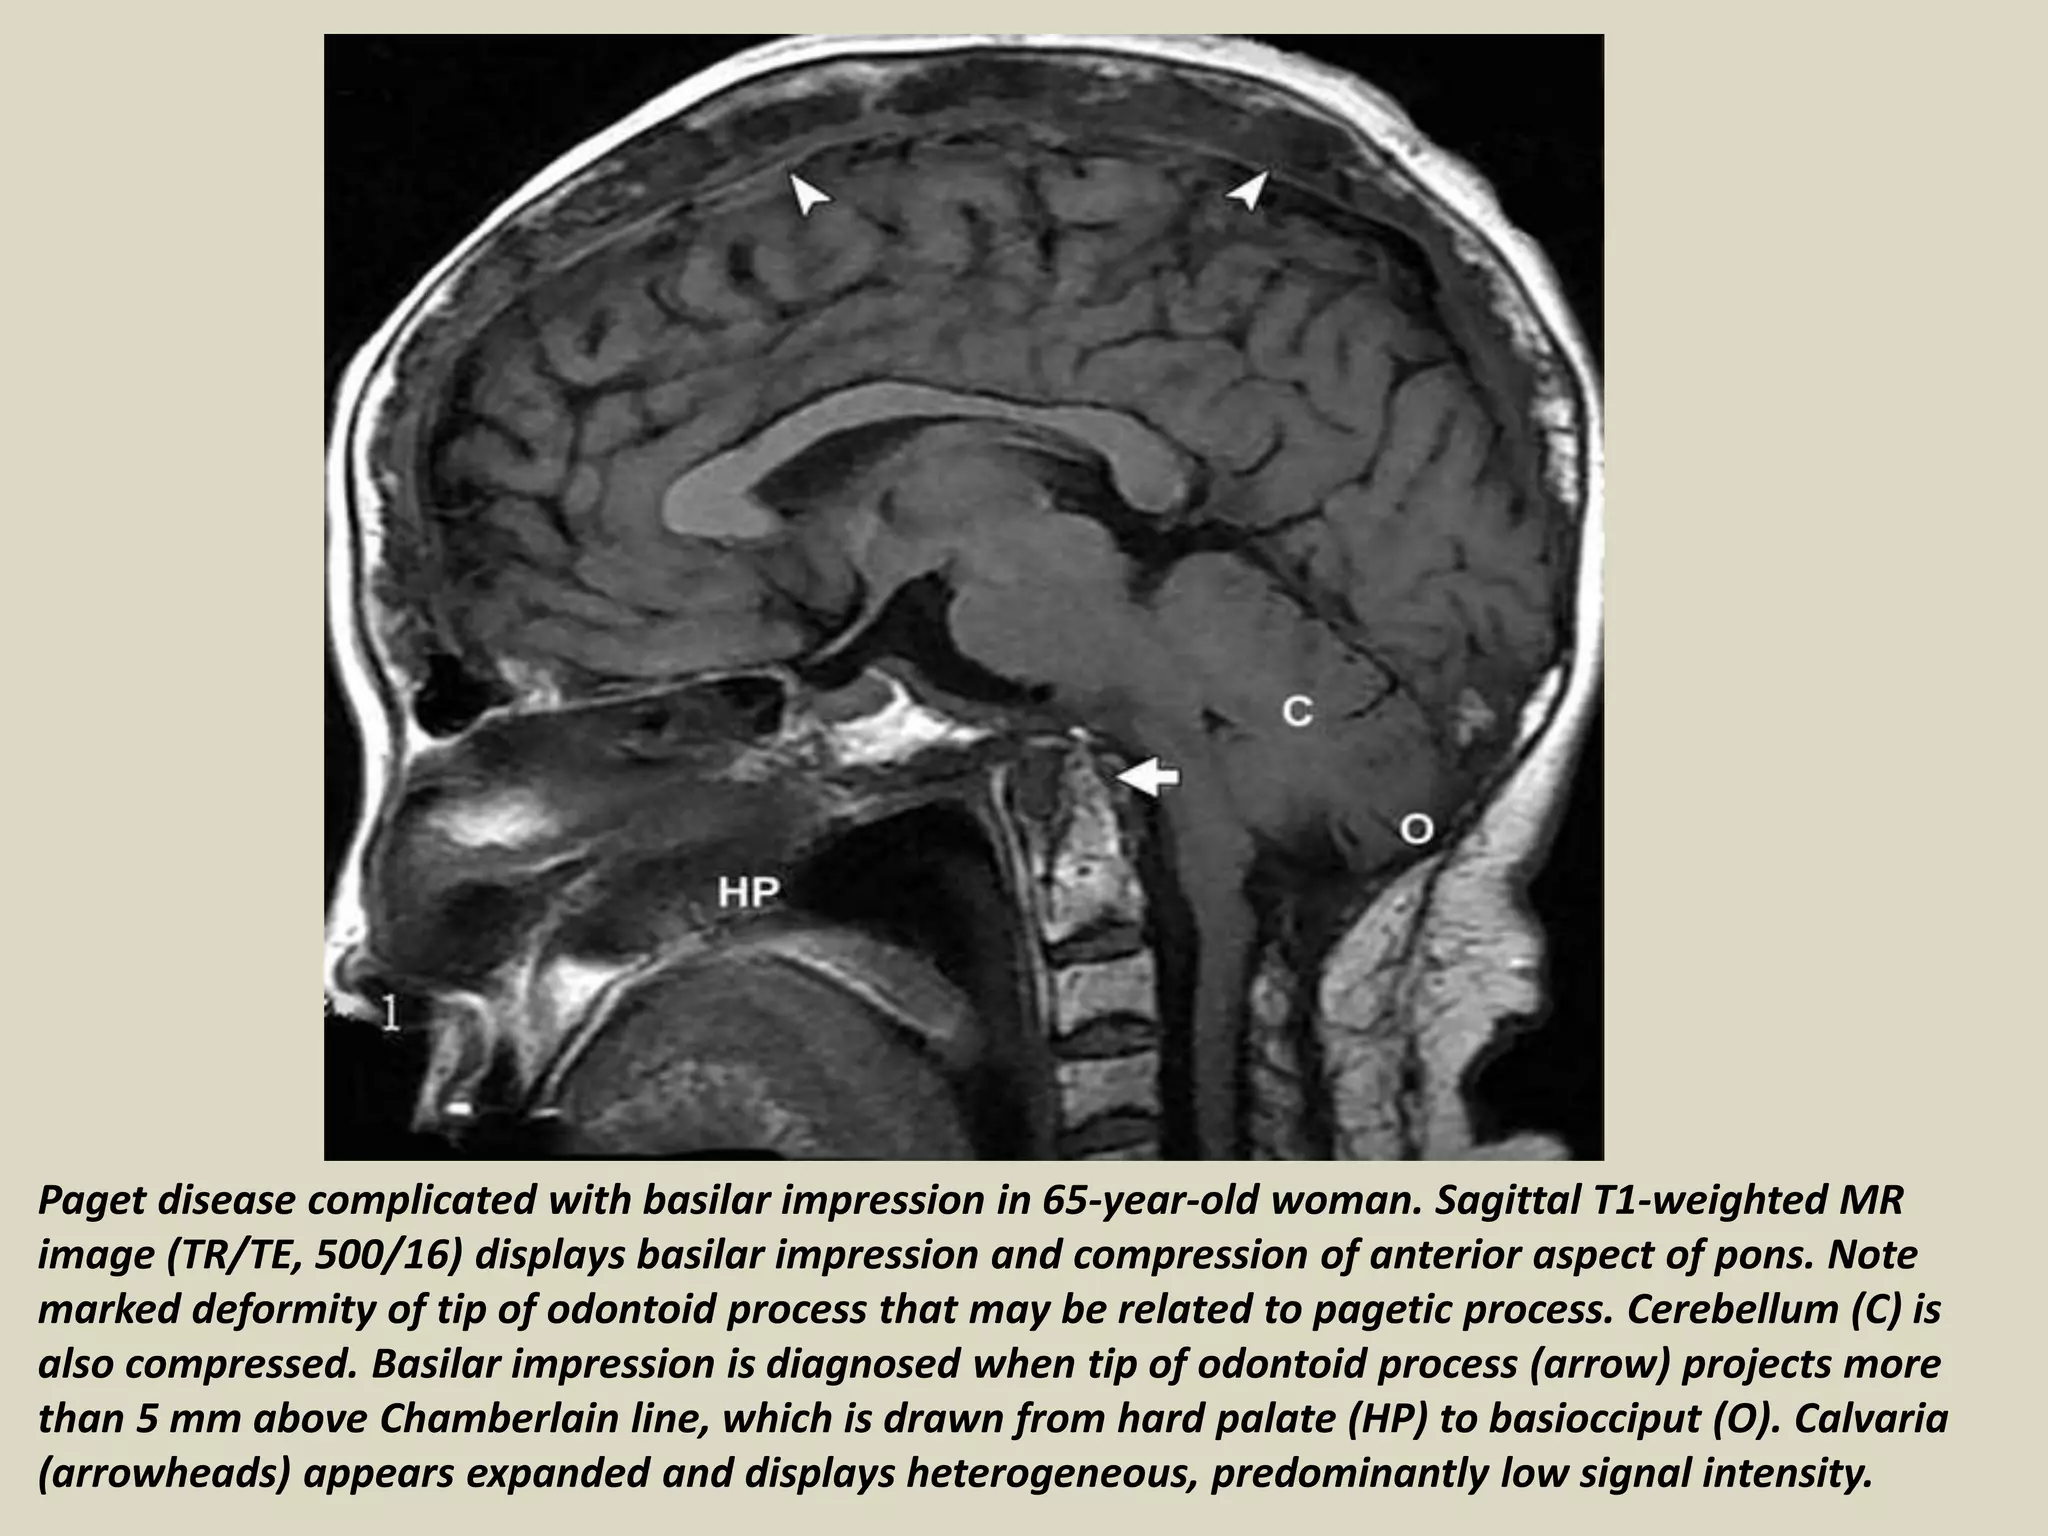

Paget disease complicated with basilar impression in 65-year-old woman. Sagittal T1-weighted MR

image (TR/TE, 500/16) displays basilar impression and compression of anterior aspect of pons. Note

marked deformity of tip of odontoid process that may be related to pagetic process. Cerebellum (C) is

also compressed. Basilar impression is diagnosed when tip of odontoid process (arrow) projects more

than 5 mm above Chamberlain line, which is drawn from hard palate (HP) to basiocciput (O). Calvaria

(arrowheads) appears expanded and displays heterogeneous, predominantly low signal intensity.